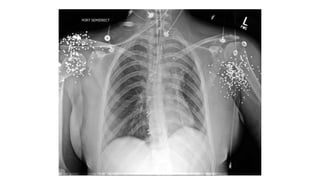

What Are You Worried About?

No Pulse

Left Arm!

Gunshot Wound

To The Neck…

Injury To The Trachea & Esophagus

Pneumomediastinum